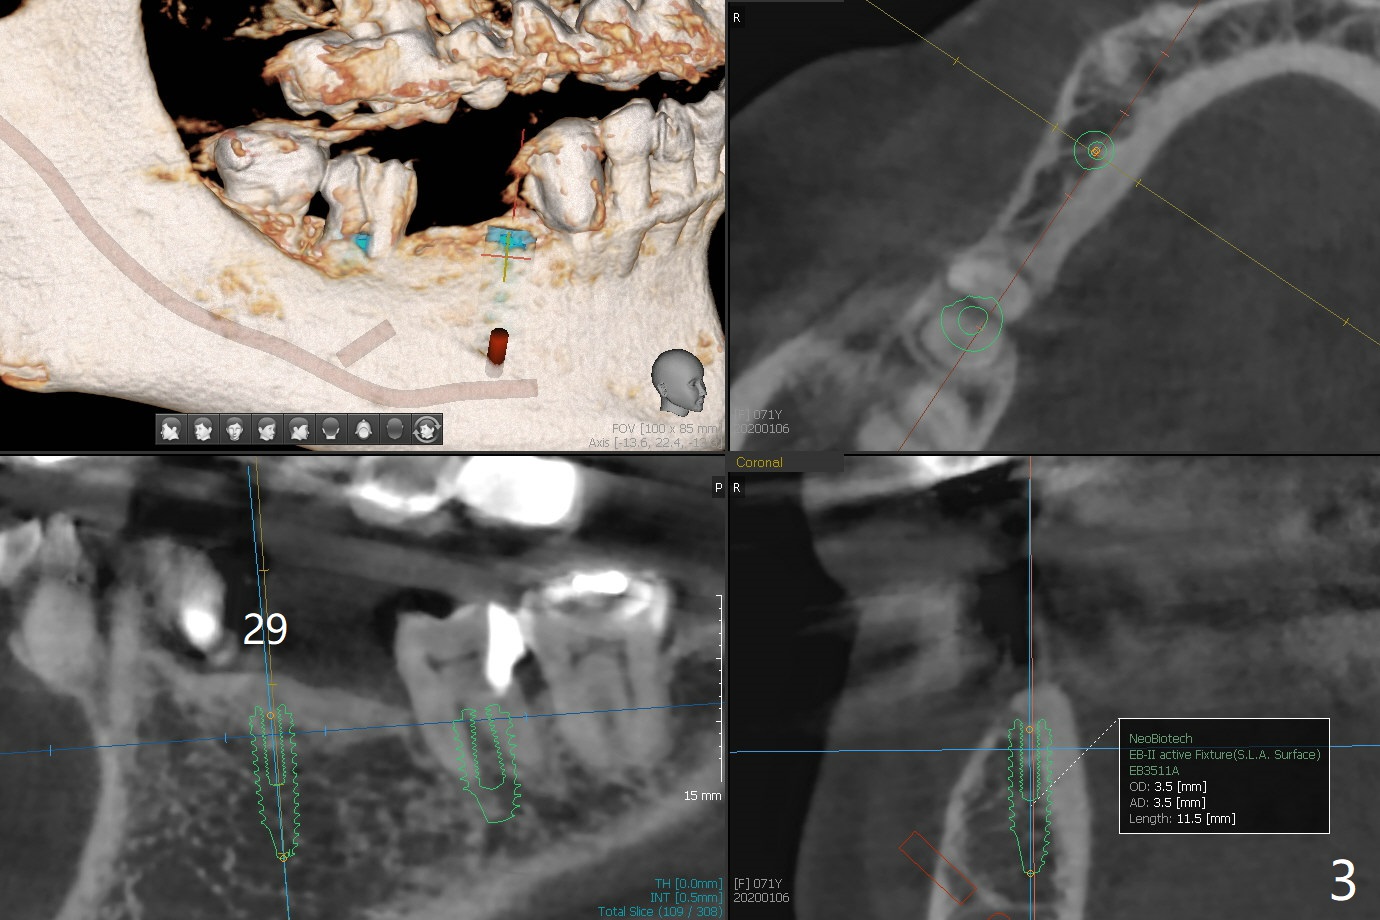

A 71-year-old woman has failed retainer at #31 (Fig.1). Implants will be placed at #31 and 29 for a FPD (Fig.2,3, as compared to Fig.4,5). The ridge at #29 is narrow with thick lingual plate. To avoid buccal deviation, coronal osteotomy overprep will be conducted.